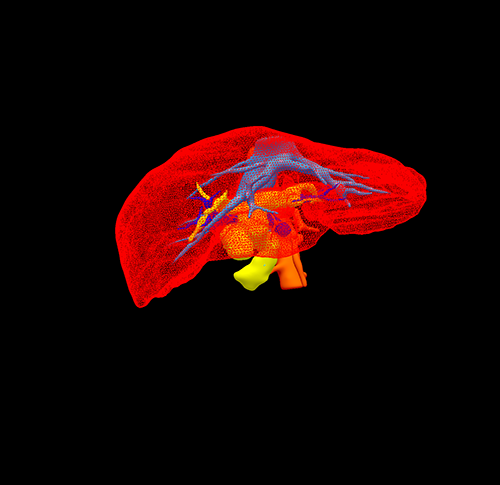

三维重建

肝内外胆管结石-腹腔镜左半肝切除、 胆囊切除、胆总管切开取石、T管引流